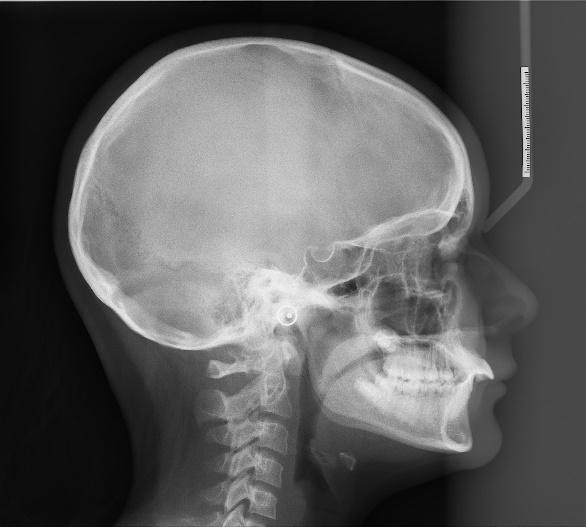

Orthodontie vestibulaire

Les progrès en matériau de collage et en métallotechnie permettent de proposer des appareillages plus modernes métalliques et en céramique pour le confort du patient et une pratique plus aisée